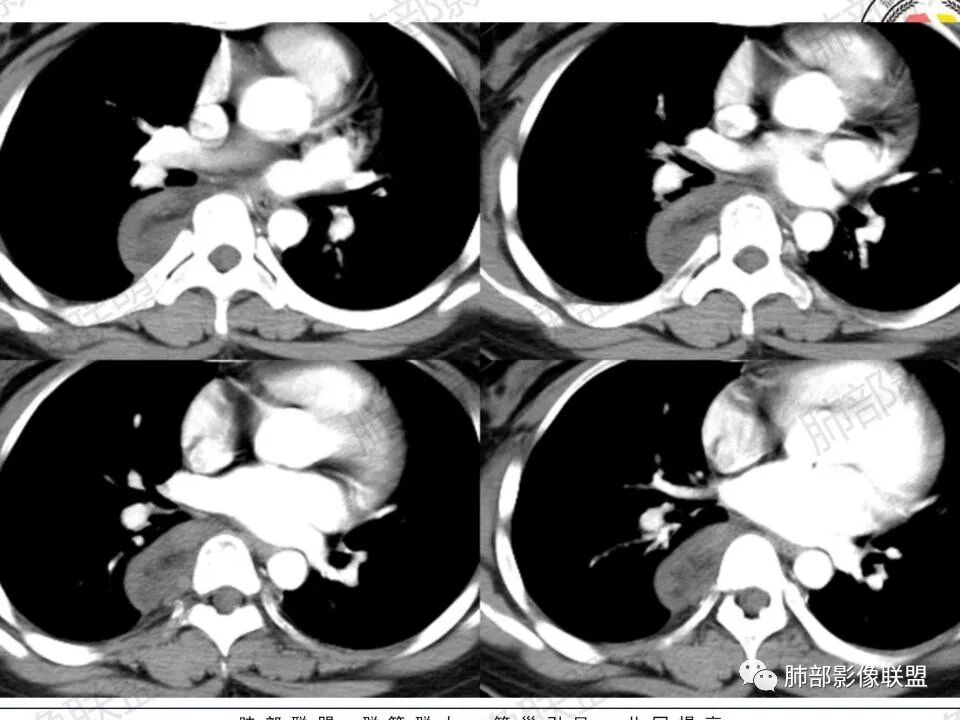

瘤体体积常较大,大部分有完整包膜,边界清楚,可沿周围组织间隙嵌入性生长,由于肿瘤质地较软,使得肿瘤可呈多种形态,其易沿着周围组织间隙生长、包饶,但不挤压周围器官或组织,邻近血管被包绕或穿行,呈嵌入式或铸型生长方式,这是后纵隔神经节细胞瘤的特征性表现;

还有另外一种形态学特征,瘤体的上下径线常大于其他径线,这可能是神经节细胞瘤起源于交感神经节,而交感神经节纵向分布于近脊柱中线两旁及前方,导致了后纵隔神经节细胞瘤纵向生长的范围大于向其他方向生长的范围,其上下可跨越多个椎体。但后纵隔神经节细胞瘤体积较小时,则常呈圆形、椭圆形、哑铃形等形态,紧贴后纵隔或后胸壁。

CT上大部分的后纵隔神经节细胞瘤呈较均匀性低密度或稍低密度影,低于肌肉密度,这主要是由于瘤体的密度根据其内含有不同比例的黏液基质与节细胞纤维成份而不同,cT值一般约20~40 HU 但其多数密度均匀,部分甚至可接近囊性低密度,这与组织学上神经节细胞胞浆丰富,瘤内含有大量黏液基质相关。MRI 上后纵隔神经节细胞瘤多呈 T1wl 低信号T2wl稍高/高信号,其中夹杂的低信号多为胶原纤维或施万细胞成分,这些低信号可纵横交错分布呈曲线或线状,这可认为是神经节细胞瘤的特征性MR表现,本组3例可见该征象。有学者报道,部分神经节细胞瘤可出现脂肪密度信号影,后纵隔肿瘤内出现脂肪密度/信号是诊断神经节细胞瘤的一种较特异性表现。神经节细胞瘤的钙化率20%~42%,钙化多呈斑点状,很少出现不规则或不均质的形态,散在点状或沙粒状是神经节细胞瘤的特征,而粗大条状或不定形则倾向恶性。

后纵隔神经节细胞瘤常动脉期无明显強化、或轻度间隔、包膜或瘤体强化,延迟期可进一步斑片、结节状轻度或中度强化,强化程度进行增加,呈渐进性延迟强化,但強化程度一般为轻度到中度强化,究其原因可能是神经节细胞瘤瘤体内含有大量黏液基质和胶原纤维,使得细胞外间隙扩大,阻碍了对比剂的灌注,从而延缓了对比剂的积累,因此其动脉期多无明显强化或仅有轻度强化,延迟期呈渐进性轻度强化是后纵隔神经节细胞瘤强化特征。大部分病灶有轻度-中度强化,部分病灶无强化,这还可能与瘤组织内部间质血管含量多少相关,无强化病例瘤组织内部主要由胶质纤维和节细胞组成,间质血管较少,因此强化较低,而强化程度较高的病理可见较多的扩张、充血的毛细血管,引起较多的对比剂积蓄,因此强化相对明显。因此,神经节细胞瘤极少出现瘤组织早期强化,而多呈延长渐进性强化,增强扫描神经节细胞瘤内细胞成分可增强,黏液基质不强化。

总结:后纵隔神经节细胞瘤的影像学表现有一定特征性:其好发于儿童或青少年,女性多见,肿瘤常位于后上纵隔,瘤体较大,上下径大于其他径线,常呈嵌入式生长方式,包饶或推挤邻近器官、血管,边界清楚。CT 平扫肿瘤多数呈均匀低密度,低于肌肉密度,瘤内钙化大多为散在斑点状钙化,偶尔出现脂肪密度是特征性表现。MR平扫呈长T1长T2信号, 有时可见瘤内低信号(胶原纤维)。增强扫描早期无明显强化或轻度强化,延迟渐进陛轻度强化是其特征。